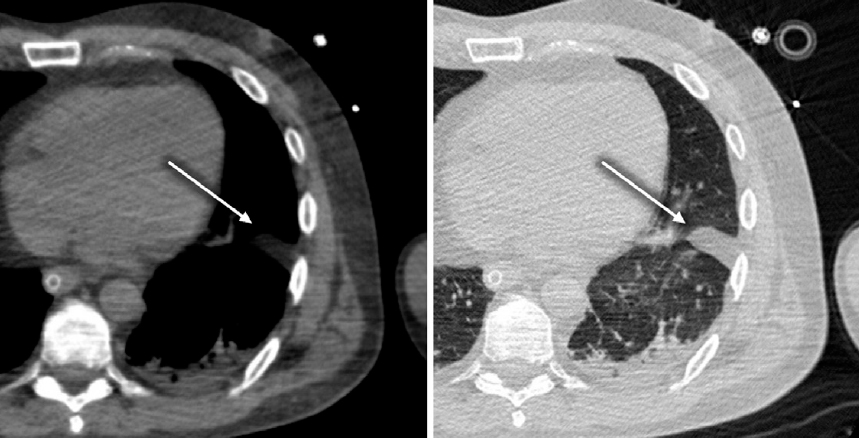

Visualization of the EPS, similar to that of the pleural cavity, is challenging on CT because the normal thickness of these anatomical structures is <1 mm. However, some patients had an increased volume of extrapleural fat. This fat may be localized along the costal pleura and in the interlobar fissures, making it visible on imaging. On lung window CT images, this pattern may mimic fluid accumulation in the pleural cavity. Differential diagnosis involves measuring the radiodensity of the observed changes: values range from –100 to –60 HU for adipose tissue and from +5 to +60 HU for fluid (Fig. 2).

Fig. 2. Chest CT in the axial plane (left: soft tissue window, right: lung window). Prolapse of extrapleural fat into the interlobar fissure (arrows).

Рис. 2. КТ органов груди в аксиальной плоскости (слева — мягкотканное окно, справа — легочное окно). Пролабирование экстраплевральной клетчатки в междолевую щель (стрелки).